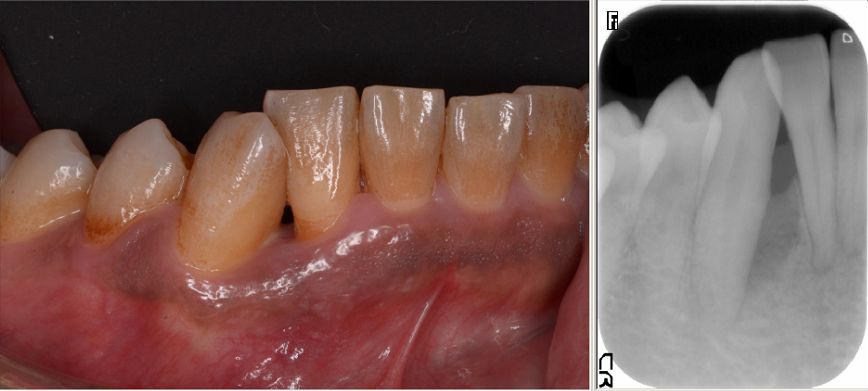

角化歯肉移植 長持ちするインプラントのために

インプラント周囲にはできれば角化した強い歯肉があったほうが

良いとされています。

GBRをおこない歯ブラシのあてにくい可動粘膜になってしまったため

上顎から歯肉を移植して強い歯肉をつくりました。

こうすることによって安定した環境を作ることができ

インプラントの長持ちにつながります。